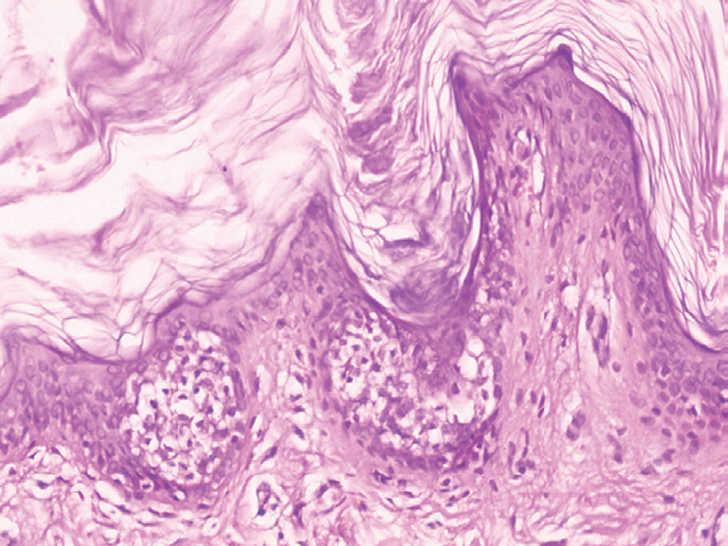

Las exploraciones complementarias realizadas incluyeron una biopsia «en sacabocados» de una zona de piel afectada (figs. 3 y 4) y una analítica general. La analítica general, en la que se incluyeron un hemograma y una bioquímica básica, no mostró alteración alguna.

Fig. 3.--Hiperqueratosis, epidermolisis suprabasal y formación de ampollas intraepidérmicas.

En el examen histopatológico de la muestra cutánea se observó una marcada hiperqueratosis, vacuolización suprabasal y formación de vesículas intraepidérmicas, es decir, un patrón de hiperqueratosis epidermolítica (figs. 3 y 4).

Como se ha comentado antes, para establecer el diagnóstico de un NEE, además de disponer de lesiones cutáneas clínicamente compatibles, es necesario realizar una biopsia cutánea para estudio histopatológico y demostrar en ella la presencia de una hiperqueratosis epidermolítica. Esta última se define como aquel patrón histológico en el que se encuentra una hiperqueratosis compacta, junto con degeneración granular y vacuolar de las capas espinosa y granulosa de la epidermis 7.